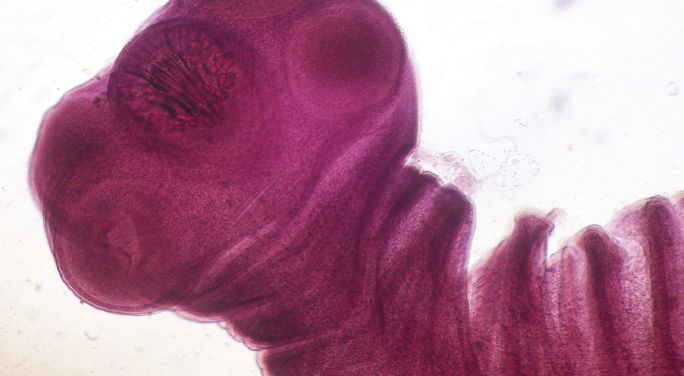

Taenia solium (TS) es un cestodo. Los humanos son los únicos hospederos definitivos, mientras que tanto los cerdos como los humanos pueden ser hospederos intermediarios. El parásito en su fase adulta habita en el tubo digestivo de los humanos (teniosis), adherido a la pared intestinal. Cada día el portador expulsa con las heces varios proglótidos1,3. Cuando los cerdos ingieren los proglótidos, los huevos que contienen atraviesan la pared intestinal y llegan al torrente sanguíneo para finalizar, sobre todo, en músculo estriado y cerebro donde se transforman en larvas (cisticercos). Los humanos se infectan ingiriendo carne de cerdo infestada y con un proceso insuficiente de cocción3,4. Una vez en el intestino delgado, las larvas se evaginan, el escólex se adhiere a la pared intestinal, la tenia crece y el ciclo se repite.

La cisticercosis humana se adquiere de manera accidental cuando el hombre ingiere los huevos por transmisión feco-oral. Como en el cerdo, los huevos se transformarán en cisticercos y se distribuirán por los tejidos del hombre, músculo estriado, corazón, tejido subcutáneo, ojo y cerebro. Esta última localización es la más grave y la enfermedad que provoca recibe el nombre de neurocisticercosis (NCC)3,4,11.